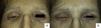

Presentamos el caso de una mujer de 55 años de edad, diagnosticada de carcinoma lobulillar de mama de 15 años de evolución. Esta fue remitida a nuestra unidad por lesiones de un año de evolución que se habían originado en la región cervical y extendido hacia el tercio superior de espalda y tórax. En la exploración clínica, presentaba pápulas y placas eritematoedematosas de consistencia dura, bien definidas en la región cervical posterior (fig. 1), así como eritema localizado en los 4 párpados que infiltraba a planos profundos dificultando la apertura (fig. 2a) y cierre (fig. 2b) de la hendidura palpebral.

Dentro de las tumoraciones en párpados, las metástasis cutáneas son excepcionales y representan menos del 1% de las lesiones malignas en párpados5. Se han descrito 3 formas clínicas: la nodular es la forma más frecuente, caracterizada por nódulos subcutáneos no dolorosos que clínicamente se puede confundir con un chalazión6; la de patrón inflamatorio, difuso de aspecto morfeiforme como en nuestro caso; y, por último, la forma ulcerada cuando histológicamente el infiltrado sobrepasa la dermis y alcanza la epidermis.